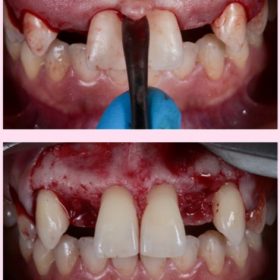

Step 3: Surgical steps from incision to implant placement.